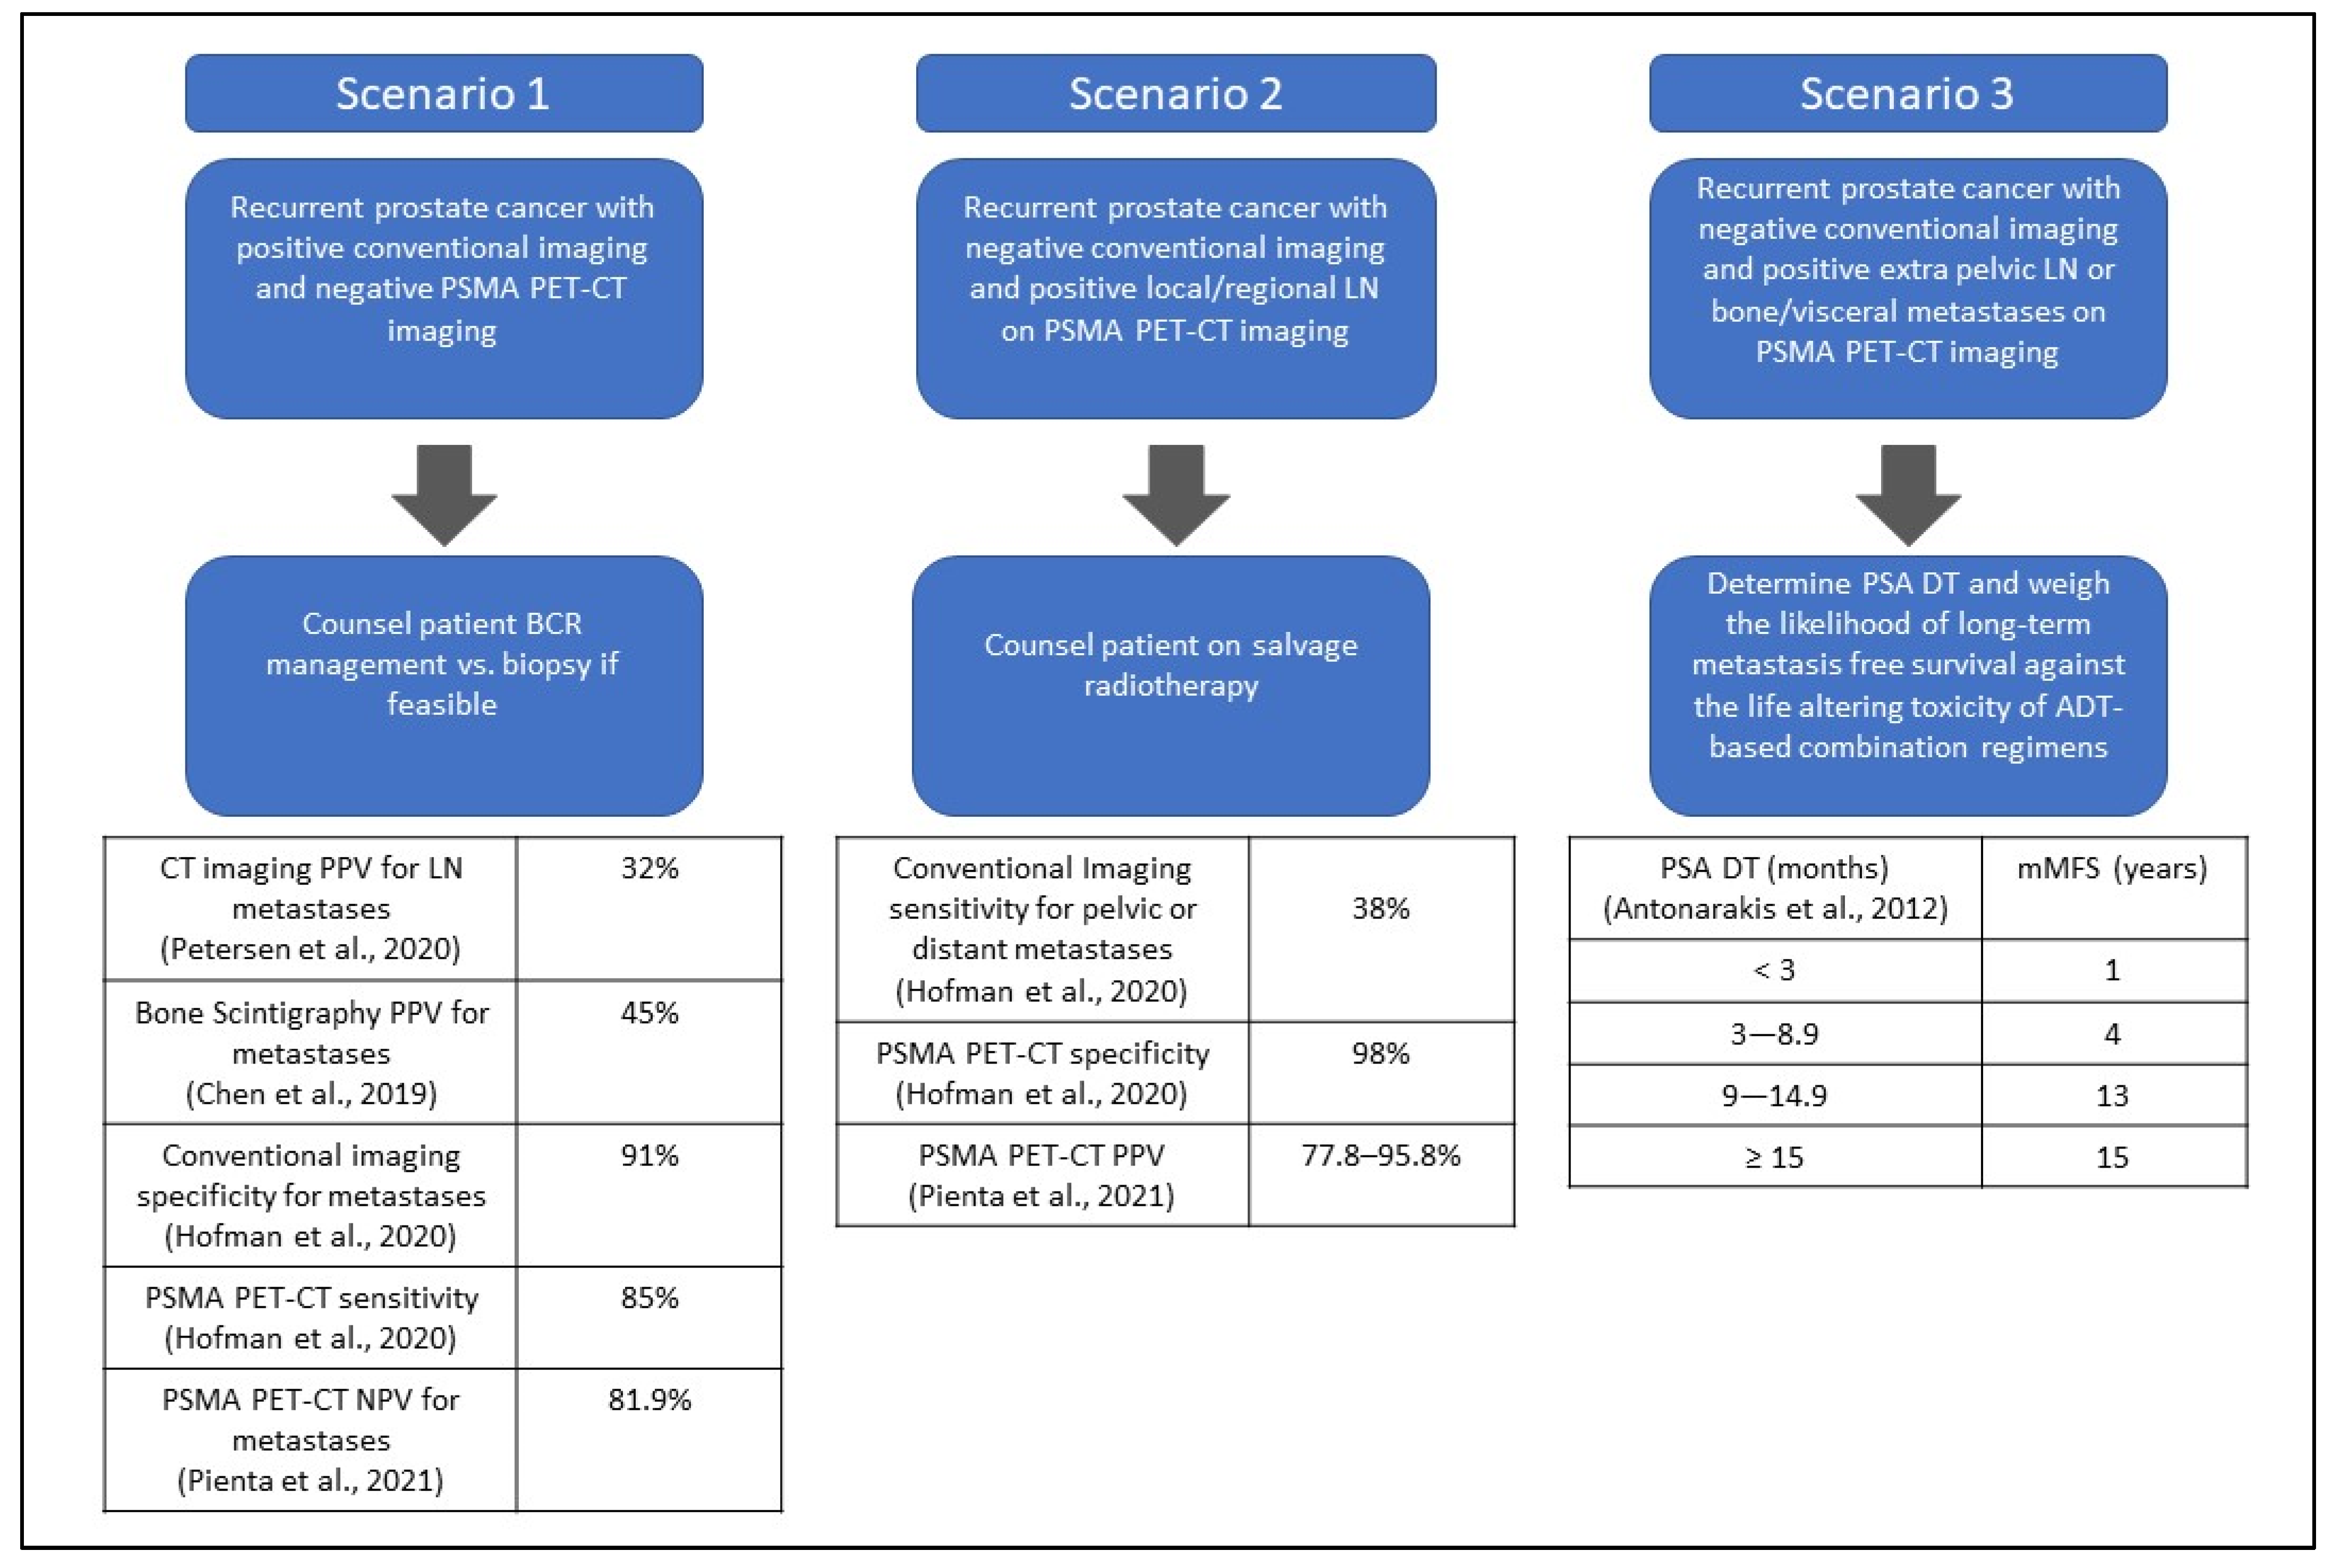

What To Do With a Positive PSMA PET and Negative Conventional Imaging in Patients With Prostate Cancer

PSMA pet scans: Just because it is more sensitive doesn't make it

Cancers, Free Full-Text

Diagnostics, Free Full-Text

Diagnostics, Free Full-Text